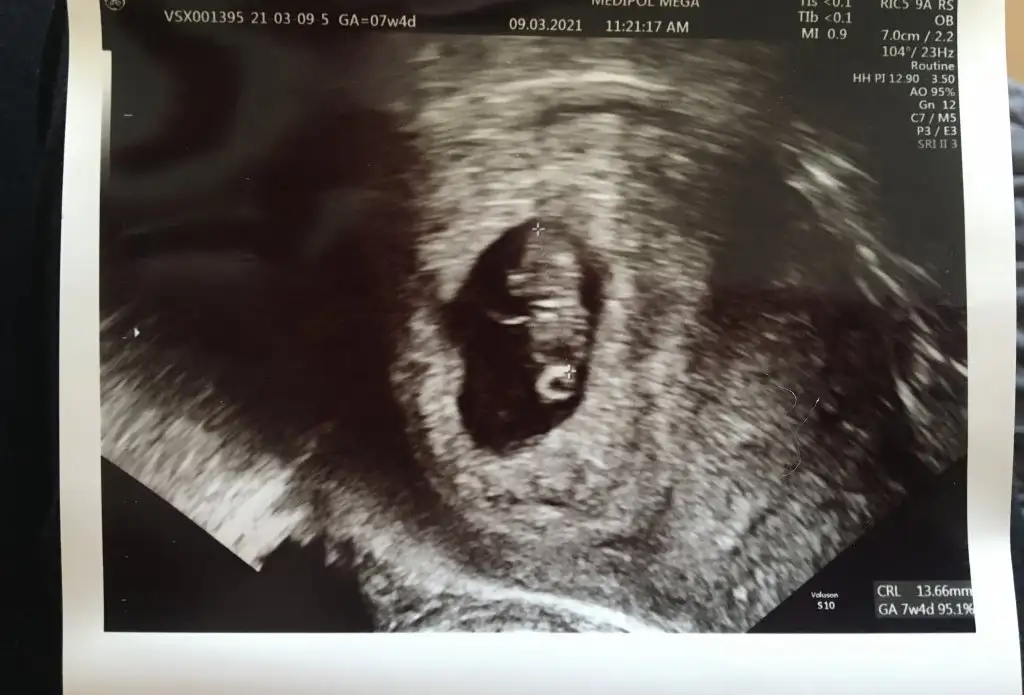

7+4 olduk bugün.

Her gidişimde kalbi durdu diyecek diye nabzım yüksek, ellerim buz gibi gidiyorum doktora.

O devasa kanamadan sonra düşüğü kabullendik derken kalp atışını duymuştuk. Bugün daha büyümüş gördük. Kalbi hala gümbür gümbür. Kanama alanı var, benim kahverengi akıntım 13 gündür devam ediyor. Bu bebek doğarsa literatüre geçersin dedi doktor

4 gün sular seller gibi kanama oldu hastanede yattım.

Fotoğrafları paylaştım vajinal ultrason. Kalbi 140 üzerinde atıyor. Kesenin solunda, kese içine doğru kanama alanı varmış allahtan bebeği sıkıştırmıyor. Yorumlayacak olan var mı?